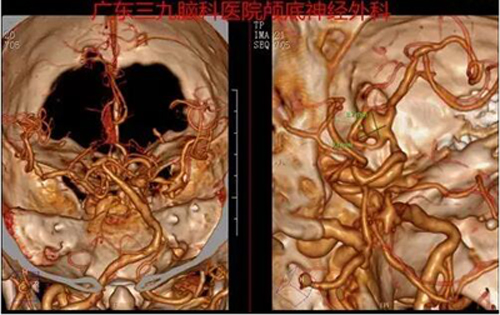

图2:术前CTA提示右侧大脑中动脉M1段分叉处示一囊状突起影,朝向前下方,范围约9.3mm×8.7mm

图3:术前DSA造影提示右侧大脑中动脉分叉处动脉瘤,大小约6mm*7mm,宽颈朝下生长,瘤体见一子瘤,大小约2mm*3mm

图4:术后DSA提示夹闭术后改变,动脉瘤未见残留,载瘤动脉显影通畅